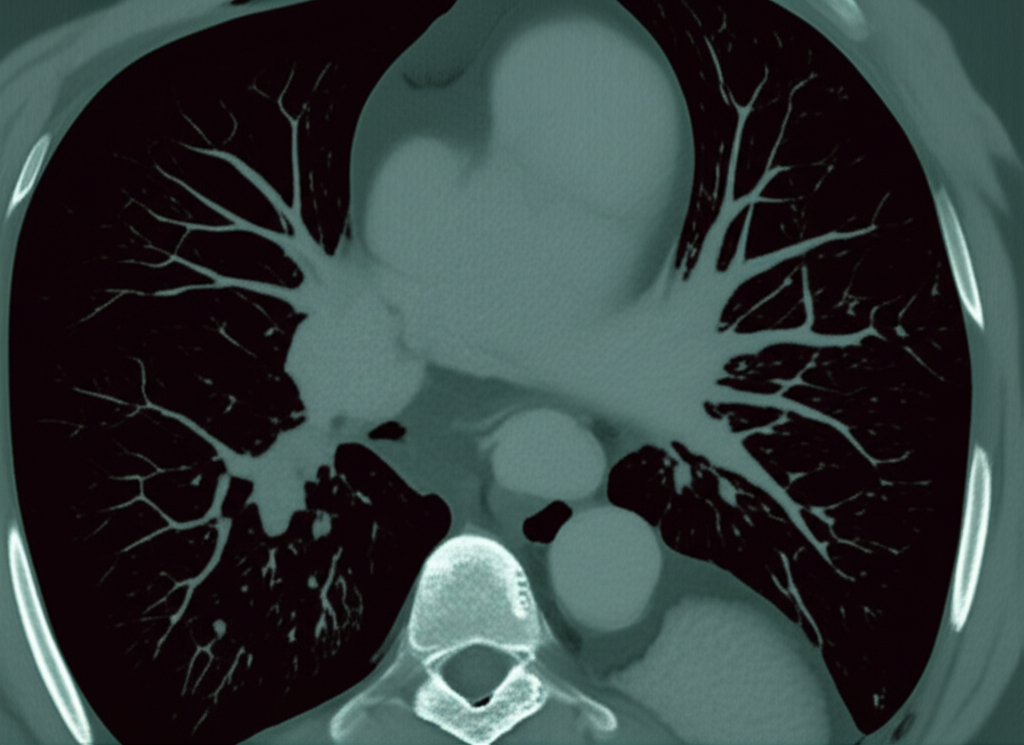

심장 CT(Computed Tomography)는 컴퓨터 단층 촬영 기술을 이용하여 심장의 단면 영상을 얻는 검사입니다. 기존의 엑스레이 촬영보다 훨씬 더 자세하고 정확한 이미지를 제공하여, 심장 질환의 조기 진단과 치료 계획 수립에 큰 도움을 줍니다. 심장 CT는 특히 관상동맥 질환, 심장 판막 질환, 심근 질환 등 다양한 심장 질환을 진단하는 데 유용합니다.

- 관상동맥 질환 진단: 관상동맥 CT는 관상동맥의 협착이나 폐쇄 여부를 정확하게 진단할 수 있습니다. 특히, 칼슘 스코어링을 통해 동맥경화의 정도를 평가하고, 향후 심혈관 질환 발생 위험을 예측할 수 있습니다.

- 심장 구조 평가: 심장의 크기, 모양, 위치 등을 정확하게 파악하여 심장 비대, 심방중격결손, 심실중격결손 등 선천성 심장 질환이나 심장 구조 이상을 진단할 수 있습니다.

- 심장 기능 평가: 심장의 수축력과 이완력을 평가하여 심부전 진단에 도움을 줄 수 있습니다. 심장 CT는 심장의 각 부위별 기능을 평가하여, 심부전의 원인을 파악하는 데 중요한 정보를 제공합니다.